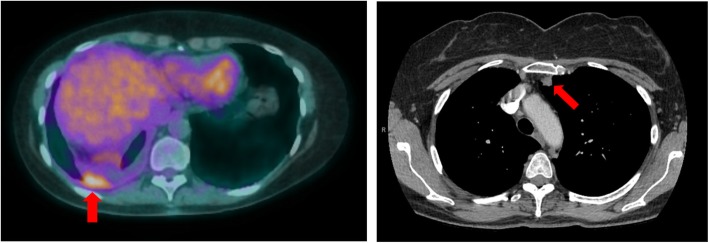

A year after her surgery, disease recurrence was documented on imaging in the right pleura. The same neoplasm was identified upon pathology review of a right pleural biopsy and she received local radiation therapy as salvage treatment. Follow up imaging in 3 months identified new lung nodules and the patient was referred to our institution. Figure 1 shows the metabolically avid right pleural thickening that was radiated and one of the lung nodules at the time of disease recurrence following radiation. Molecular analysis of the original lobectomy material with next generation sequencing revealed a BRAF V600E mutation. Subsequently, she was initiated on combination of dabrafenib and trametinib treatment in the context of a clinical trial.

Fig. 1.

Sites of disease on recurrence. Pleural thickening with metabolic activity on the right was biopsied and pathology review confirmed mucinous adenocarcinoma with predominant lepidic pattern. In 3 months following radiation therapy of the recurring pleural lesion, there were new lung nodules identified on CT scan. One of these nodules is shown at the left upper lobe on the right